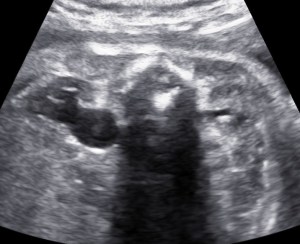

Unilateral hydronephrosis in a case of megaureter.